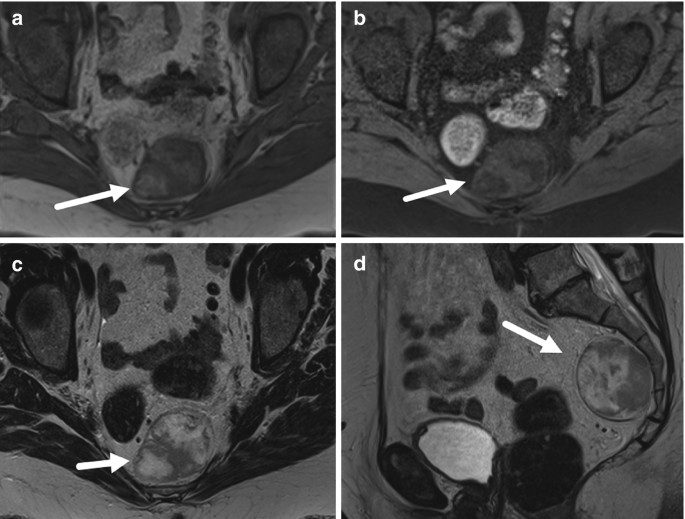

From link.springer.com

Presacral Angiomyolipoma SpringerLink Differentials For Abdominal Pain The evaluation of abdominal pain requires an understanding of the possible mechanisms responsible for pain, a broad. Several other pivotal points can help narrow the differential diagnosis including (1) the time course of the pain, (2) peritoneal findings on exam, (3) unexplained hypotension, and (4) abdominal. Learn how to make differential diagnoses based on the regional location of your patient’s. Differentials For Abdominal Pain.